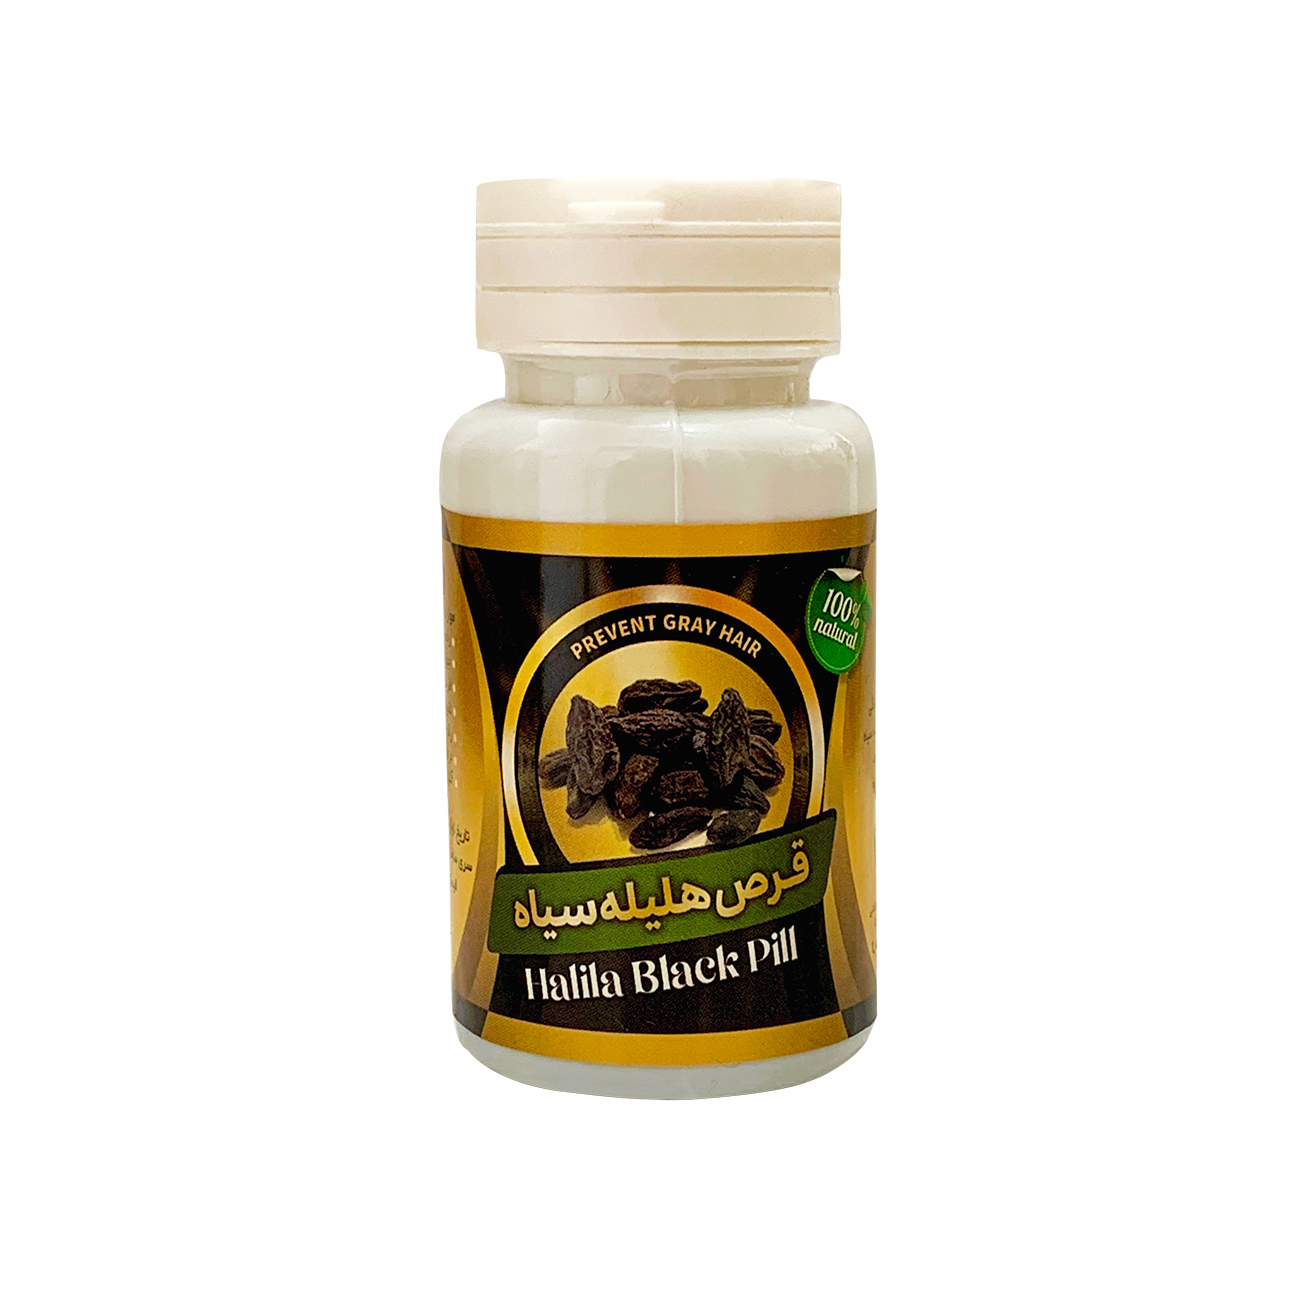

قرص گیاهی هلیله سیاه لیروسانا

ترکیبات قرص گیاهی هلیله سیاه لیروسانا:

شکر قهوه ای نیشکر،پودر هلیله سیاه

زمان و روش مصرف قرص گیاهی هلیله سیاه لیروسانا:

روزانه 3 عدد قبل غذا و ترجیحا به صورت مکیدنی

دوره مصرف کپسول هلیله سیاه 40 روز است.

موارد منع مصرف:

- کودکان زیر 6 سال

- دوران بارداری و قاعدگی